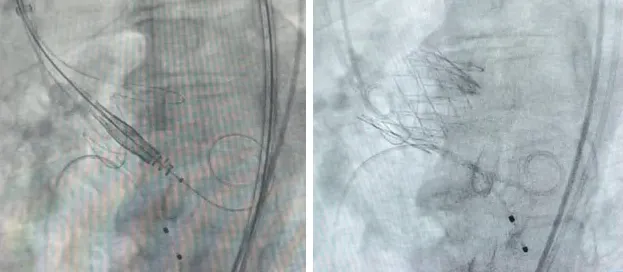

团队采用经股动脉TAVR术,成功救治一例大瓣环单纯主动脉瓣关闭不全患者。以往这类手术因瓣膜缺乏足够固定力,仅适用于部分解剖条件合适的患者。新型带定位件的经股动脉TAVR器械手术创伤更小、患者恢复更快。患者为73岁男性,因间断胸闷不适2年、加重1周入住外院,检查发现主动脉瓣重度关闭不全、心脏扩大,左心室射血分数(LVEF)降至35%,外院评估后认为不适合常规手术,遂转入朝阳医院。患者还伴有慢性肾病与贫血,身体基础条件较差。进一步检查显示,其心脏瓣环偏大,血管形态特殊,即便使用新型器械,仍存在瓣膜脱落、栓塞的高风险。针对这一复杂情况,麻醉团队协助实施镇静局麻后,手术团队小心翼翼输送瓣膜,精准调节定位件并高位植入。术后仅残余微量瓣周漏,心电图无传导阻滞情况,患者即刻清醒,顺利返回病房。

经股动脉TAVR治疗大瓣环单纯主动脉瓣关闭不全患者相关影像